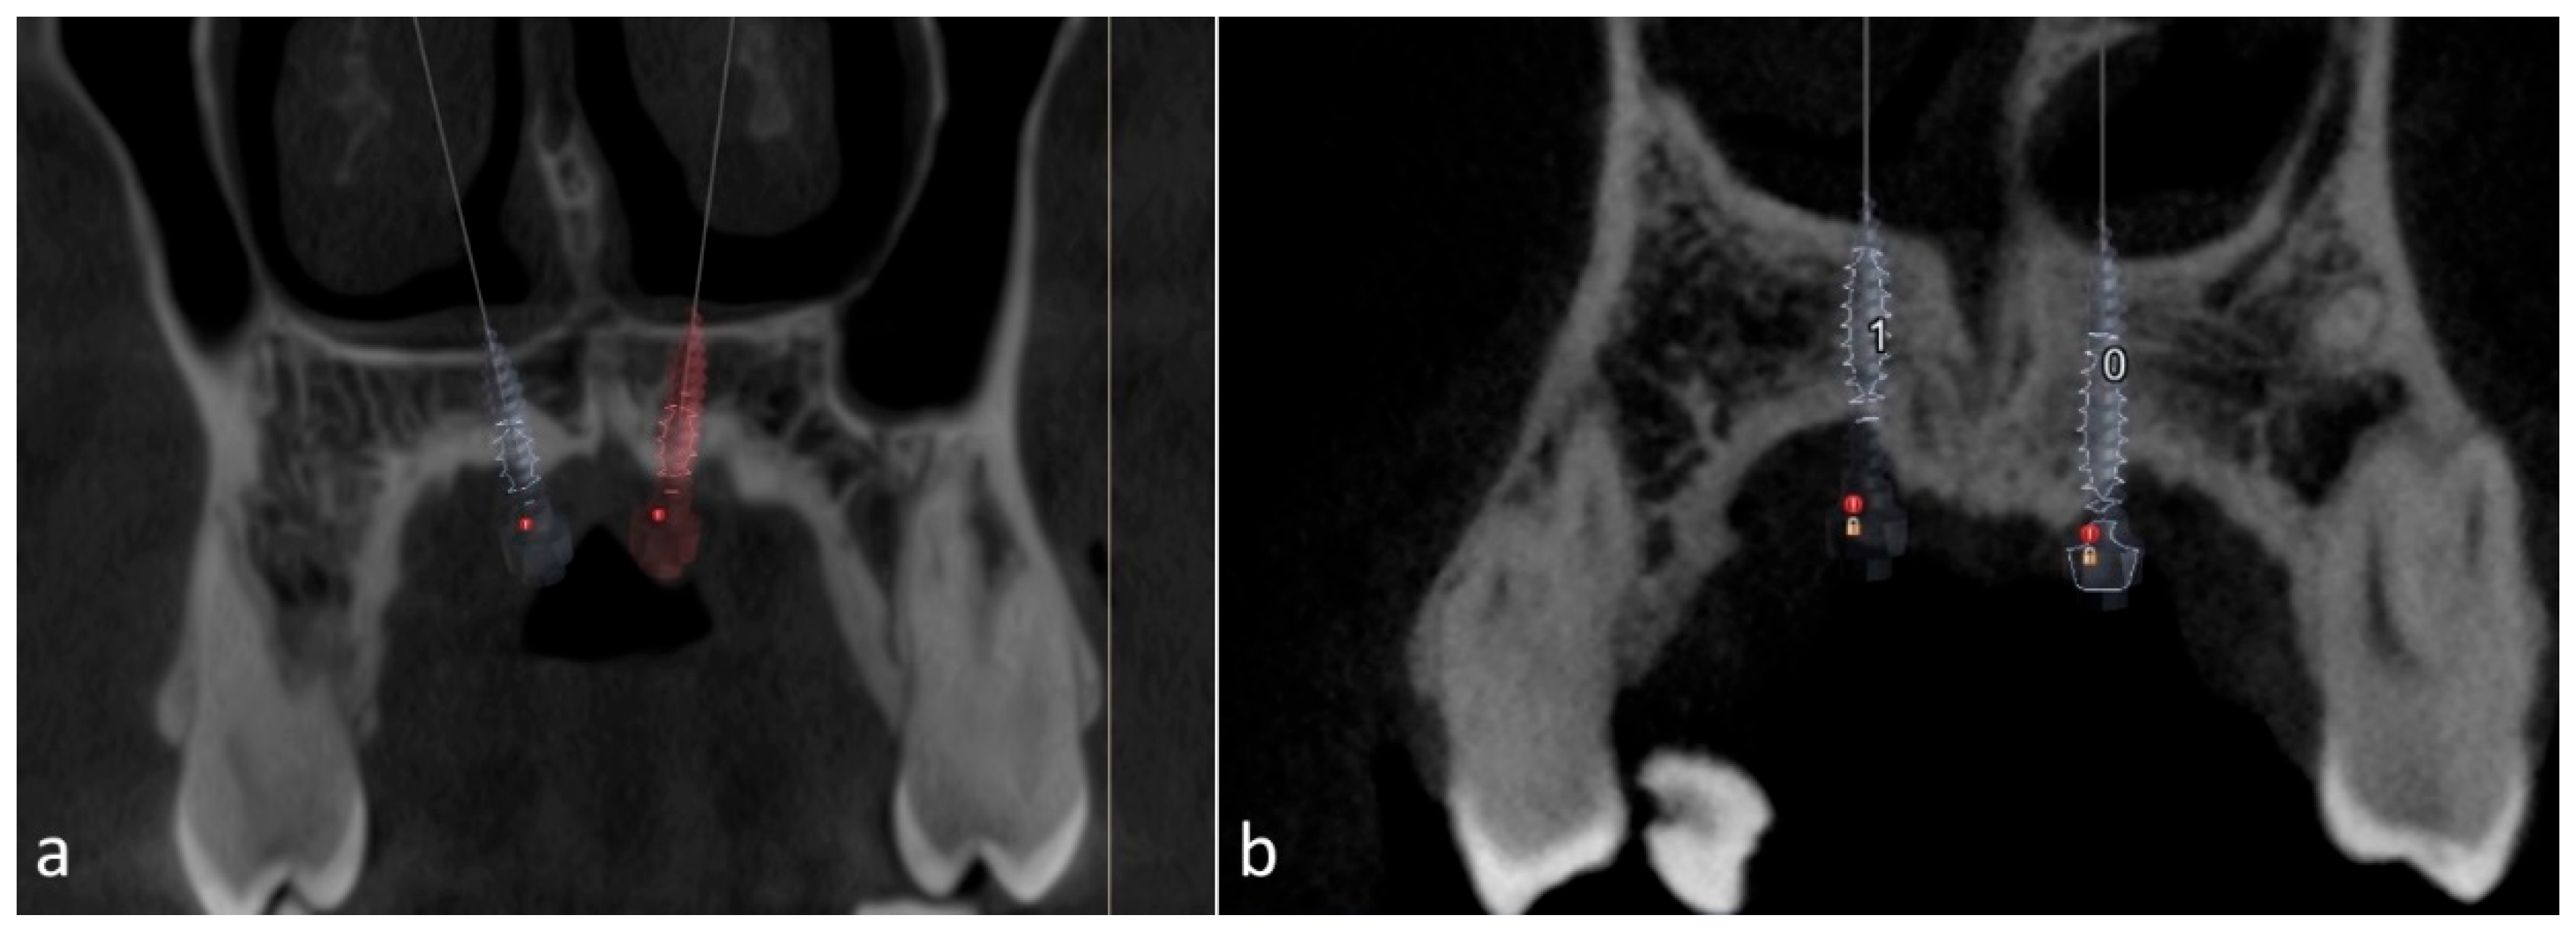

- The MSE system designed by Dr. Won Moon (Biomaterials Korea, Seoul, Republic of Korea) that has a jackscrew component with four parallel holes for mini-implant insertion and supporting arms on both sides soldered to the molar bands, aiming to stabilize the device’s position during expansion. Regularly, the position of the appliance is between the two zygomatic-maxillary buttresses, frequently located at the level of the first molars, so the mini screws are located just anteriorly to the soft palate [10,28]. An example of the posterior positioning of the MSE jackscrew with four mini-implants performed for a patient in our clinic, can be seen in Figure 2.